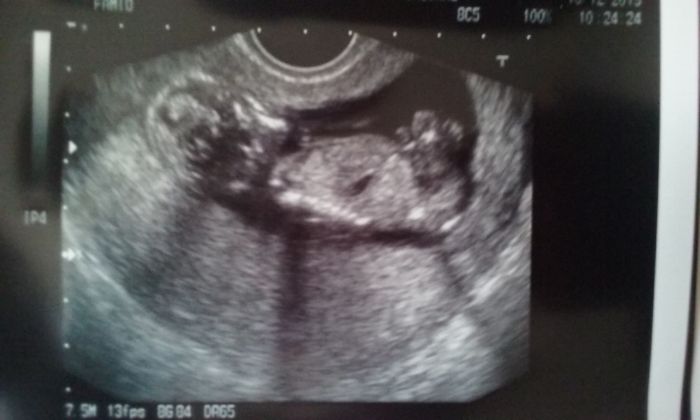

jů to je krásná fotka :) no já mám asi opravdu plavečák tak mám smůlu ale na té poslední fotce je malej taky přes celou dělohu tak nechápu moc no....25 jdu na KO tak se doktora zeptám ale to už asi nebude třeba to už budu nějaký 19 týden skoro takže to už bude cítit určitě